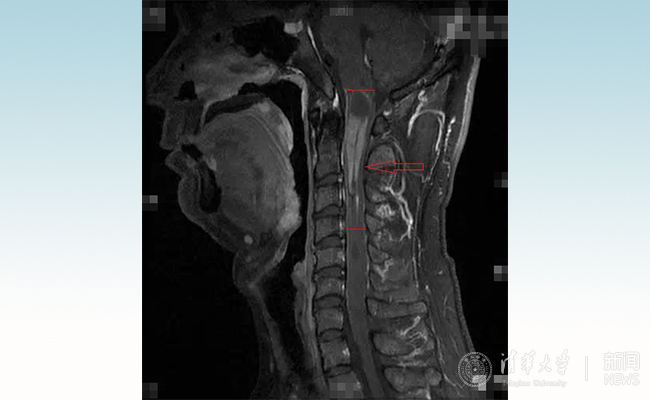

患者小智术前的核磁影像。

从人体的后脑到颈部一直向下延伸到尾椎,是一根长长的管道,里面是一根手指粗细的脊髓,它就像一根“电缆”,里面布满了导线一样的神经,大脑通过这根“电缆”下达指令,并接收来自身体各个部位的信号。而延颈髓肿瘤,上端濒临脑干禁区,下端延伸几公分甚至几十公分,挤压正常的脊髓,导致神经传导出现了严重问题,患者因此出现无力、莫名的疼痛甚至瘫痪的症状。“延髓是生命中枢,相当于总闸,牵一发动全身。”王贵怀说。